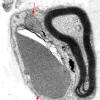

PERIPHERAL NEUROPATHY

5 AXONAL REGENERATION (8)